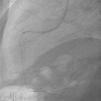

Homem, de 63 anos, recorre ao serviço de urgência do hospital mais próximo do local de férias por indisposição generalizada e dor mandibular com quatro horas de evolução, sendo diagnosticado enfarte agudo do miocárdio (EAM) da parede inferior. Já tinha antecedentes de EAM há quatro anos, em França, tendo colocado stents na coronária direita e circunflexa. Dado ser um centro sem capacidade de angioplastia, realizou fibrinólise nos primeiros 30 minutos, sendo depois transferido para centro com a mesma valência. A coronariografia revelou volumoso aneurisma no segmento médio da coronária direita em relação com porção proximal de stent, com trombo recanalizado (Figura 1). Foi tentada angioplastia para exclusão de aneurisma, mas não foi possível atravessar o stent com os fios guia utilizados. Ficou a ideia que a porção proximal do stent estaria ocluída, fazendo‐se o fluxo através da malha lateral. Dias depois fez‐se nova tentativa de angioplastia, apresentando aspeto de trombo organizado (Figura 2). Cruzou‐se a malha lateral do stent, mas não foi possível progredir um balão (Figura 3). A Figura 4 evidencia o resultado final.